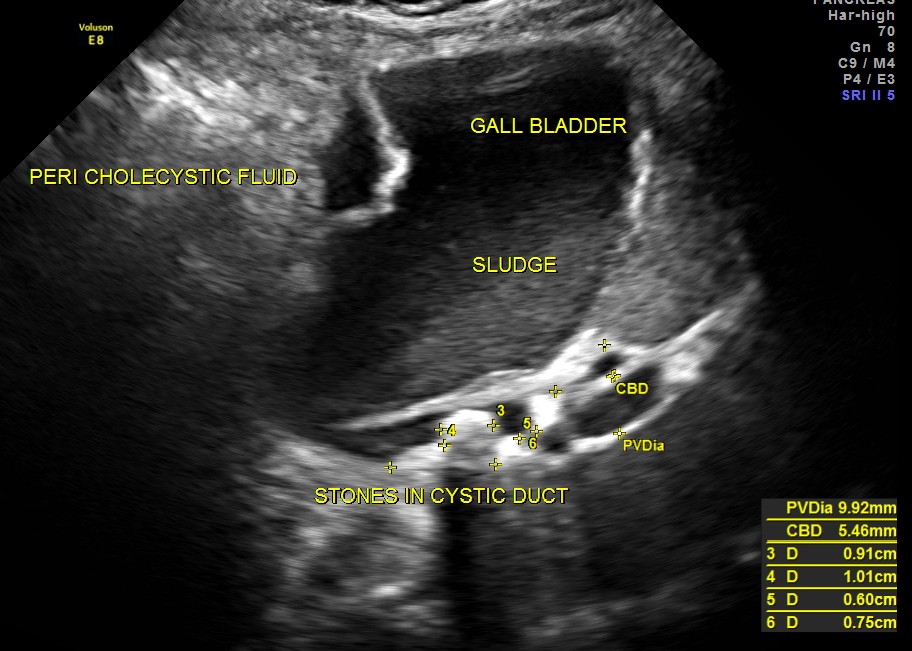

Her ultrasound showed the following findings :

grossly distended gallbladder , with sludge and gallstones and fluid around the gall bladder.

The diagnosis was : acute calculous cholecystitis , cystic duct stones causing a rupture and fluid collection around the GB and loculated sub diaphragmatic collection with reactive mild right pleural effusion . Endometrial fluid collection needed further evaluation.